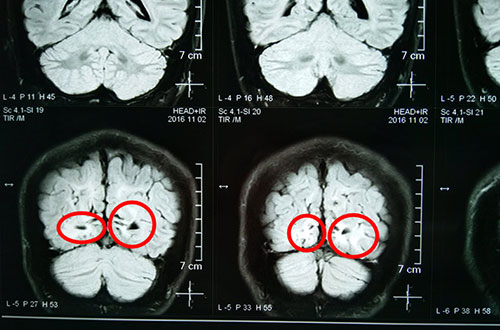

術(shù)前影像資料:紅圈內(nèi)為異常信號灶

術(shù)前影像資料:紅圈內(nèi)為異常放電區(qū)

11月2日行MR頭顱平掃+SWI,灰白質(zhì)對比成像示:雙側(cè)枕葉異常信號伴腦白質(zhì)量減少。